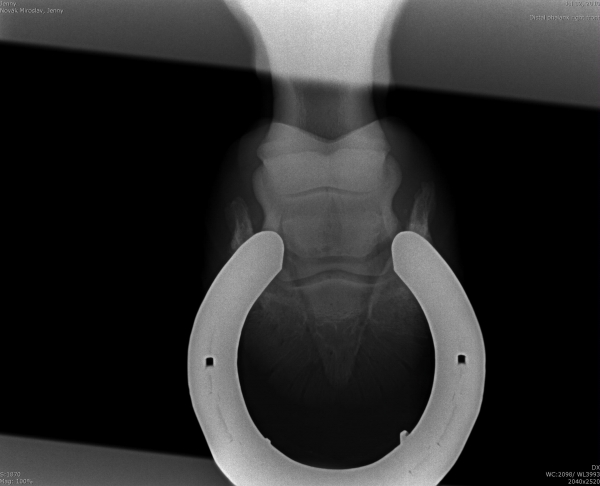

Podotrochleóza